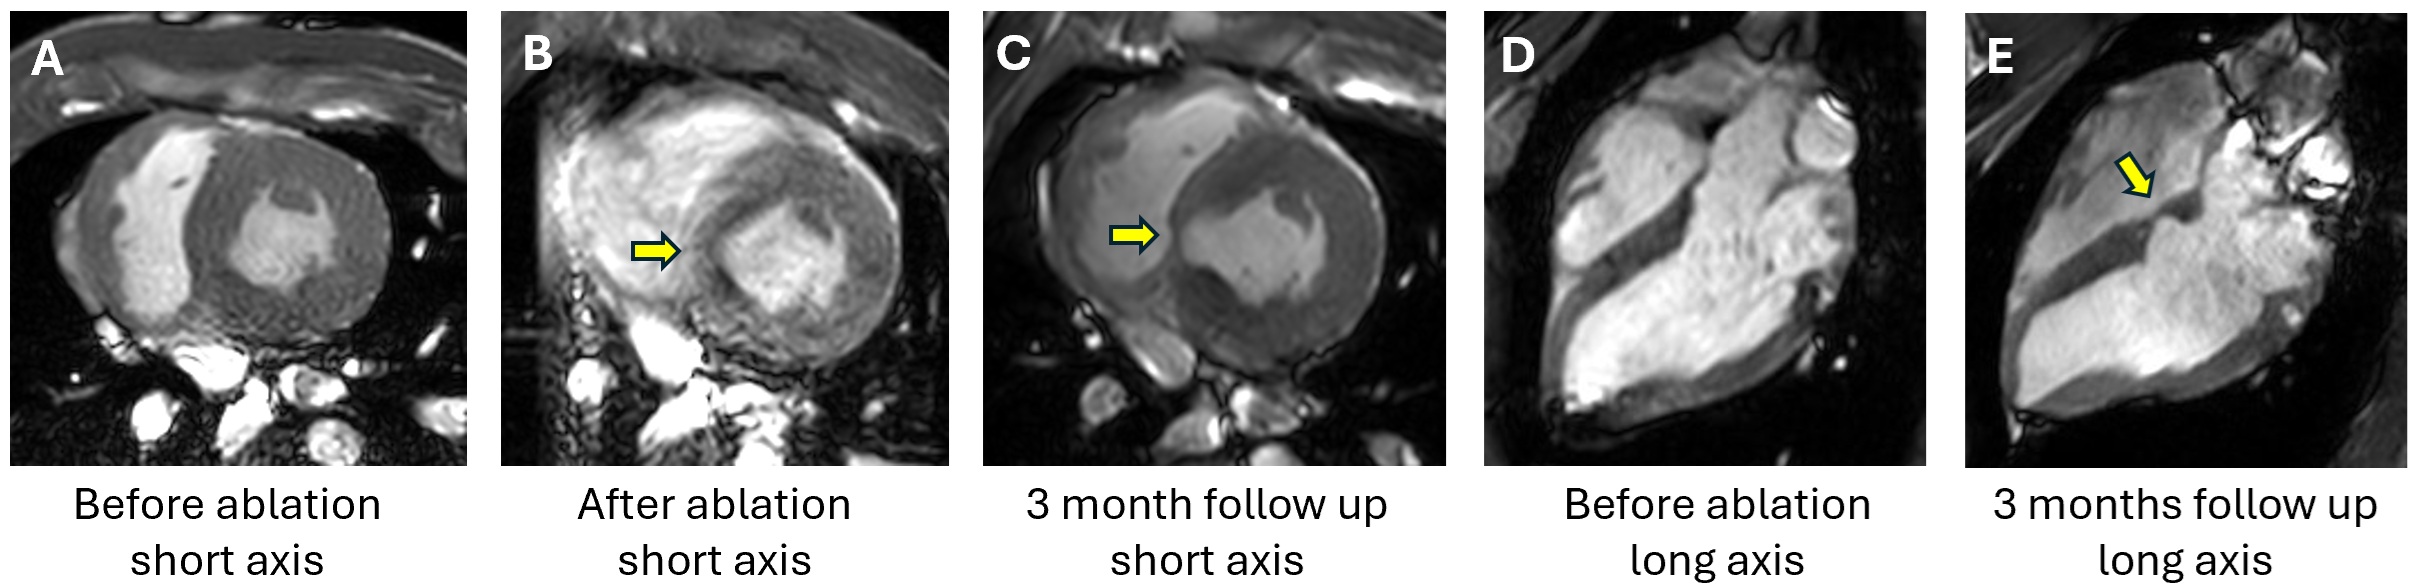

Results: HIU ablation of the IVS was effectively performed in all swine (Figure 1). Global EF decreased from 58.4±4.6% pre-ablation to 47.0±5.5% immediately post-ablation (p=0.0003) but recovered by 1- and 3-months post-procedure (Table 1). Global radial strain (GRS) decreased from 28.0 ± 4.3% at baseline to 21.0 ± 2.1 % immediately after ablation (25% decrease, p=0.0009) with subsequent recovery to 27.7 ± 1.9% by 3 months (p=0.4333) (Table 1). Global circumferential strain (GCS) decreased immediately after ablation from -16.3 ± 1.9% to -13.5 ± 0.9% (p=0.0029) but recovered to 15.6 ± 0.6% by 3 months (p=0.2038). Regional circumferential strain in the ablated region of the heart changed from -14.7±4.1% at baseline to -2.9±14.3% immediately post-ablation and increased back to -14.3±3% at 1-month follow up (Figure 2).

Conclusion: HIU catheter ablation produced deep lesions and might serve as a new modality for IVS reduction in hypertrophic cardiomyopathy. This study demonstrated temporal decrease in the LV contractility, global and regional myocardial strain after septal HIU ablation with subsequent recovery at 3-month follow up.